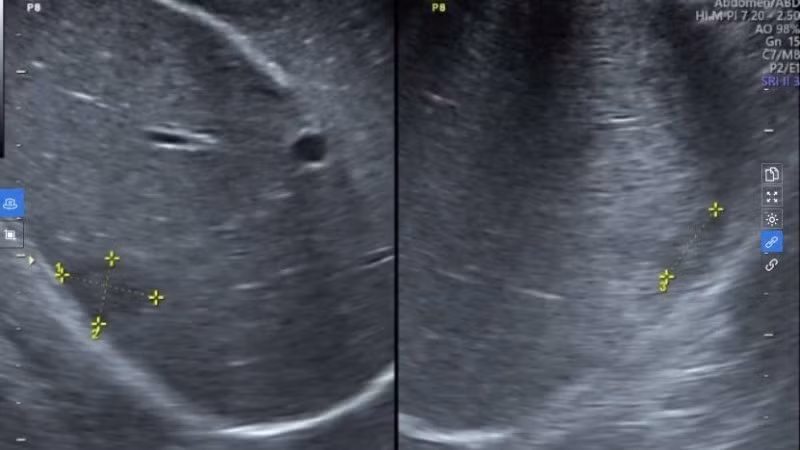

Hình ảnh siêu âm của bệnh nhân.

Kết quả của bệnh nhân cho thấy bệnh nhân có chỉ số bạch cầu ái toan tăng cao, trong máu có kháng thể IgG của sán lá gan lớn, siêu âm ổ bụng phát hiện 1 khối ở gan kích thước 39x18x20mm giới hạn không rõ, không bắt tín hiệu doppler, nằm sát vỏ bao gan, không xô đẩy các cấu trúc xung quanh. Kết quả CT phù hợp với hình ảnh tổn thương gan do ký sinh trùng (sán lá gan).

Từ kết quả khai thác các yếu tố dịch tễ, khám lâm sàng và xét nghiệm, bác sĩ Lệ kết luận bệnh nhân bị áp xe gan do sán lá gan lớn ở hạ phân thùy VII, kích thước 20x39mm, giai đoạn ổn định, không biến chứng vỡ.